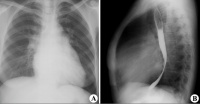

(一)X线检查:最早的改变是左心缘的左心房弧度明显,肺动脉主干突出,肺静脉增宽,右前斜位钡剂透视可见扩张的左心房压迫食道。病变严重时,左心房和右心室明显增大,后前位片示心影右缘呈双重阴影,肺门阴影加深,主动脉弓较小。左心室一般不大。当左心房压力达2.7kPa(20mmHg)时,中下肺可见KerleyB线。长期肺淤血后含铁血黄素沉积,双下肺野可出现散在的点状阴影。老年患者常有二尖瓣钙化,青壮年亦不少见。

二尖瓣狭窄